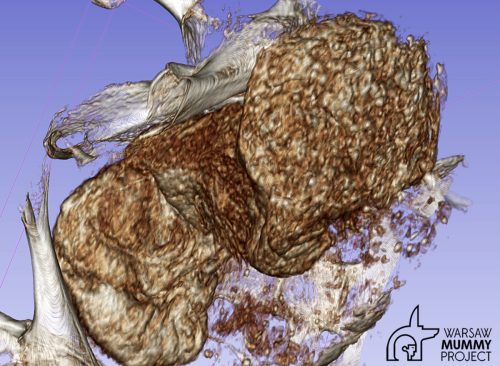

CT scans of the body enabled scientists to make two major discoveries: The woman's potential cause of death, and the likelihood that she was pregnant when she died. The fetus was detected in the lower part of the pelvis and had been mummified along with its mother. Researchers measured head circumference, determining it was between 26 and 30 weeks of gestation.